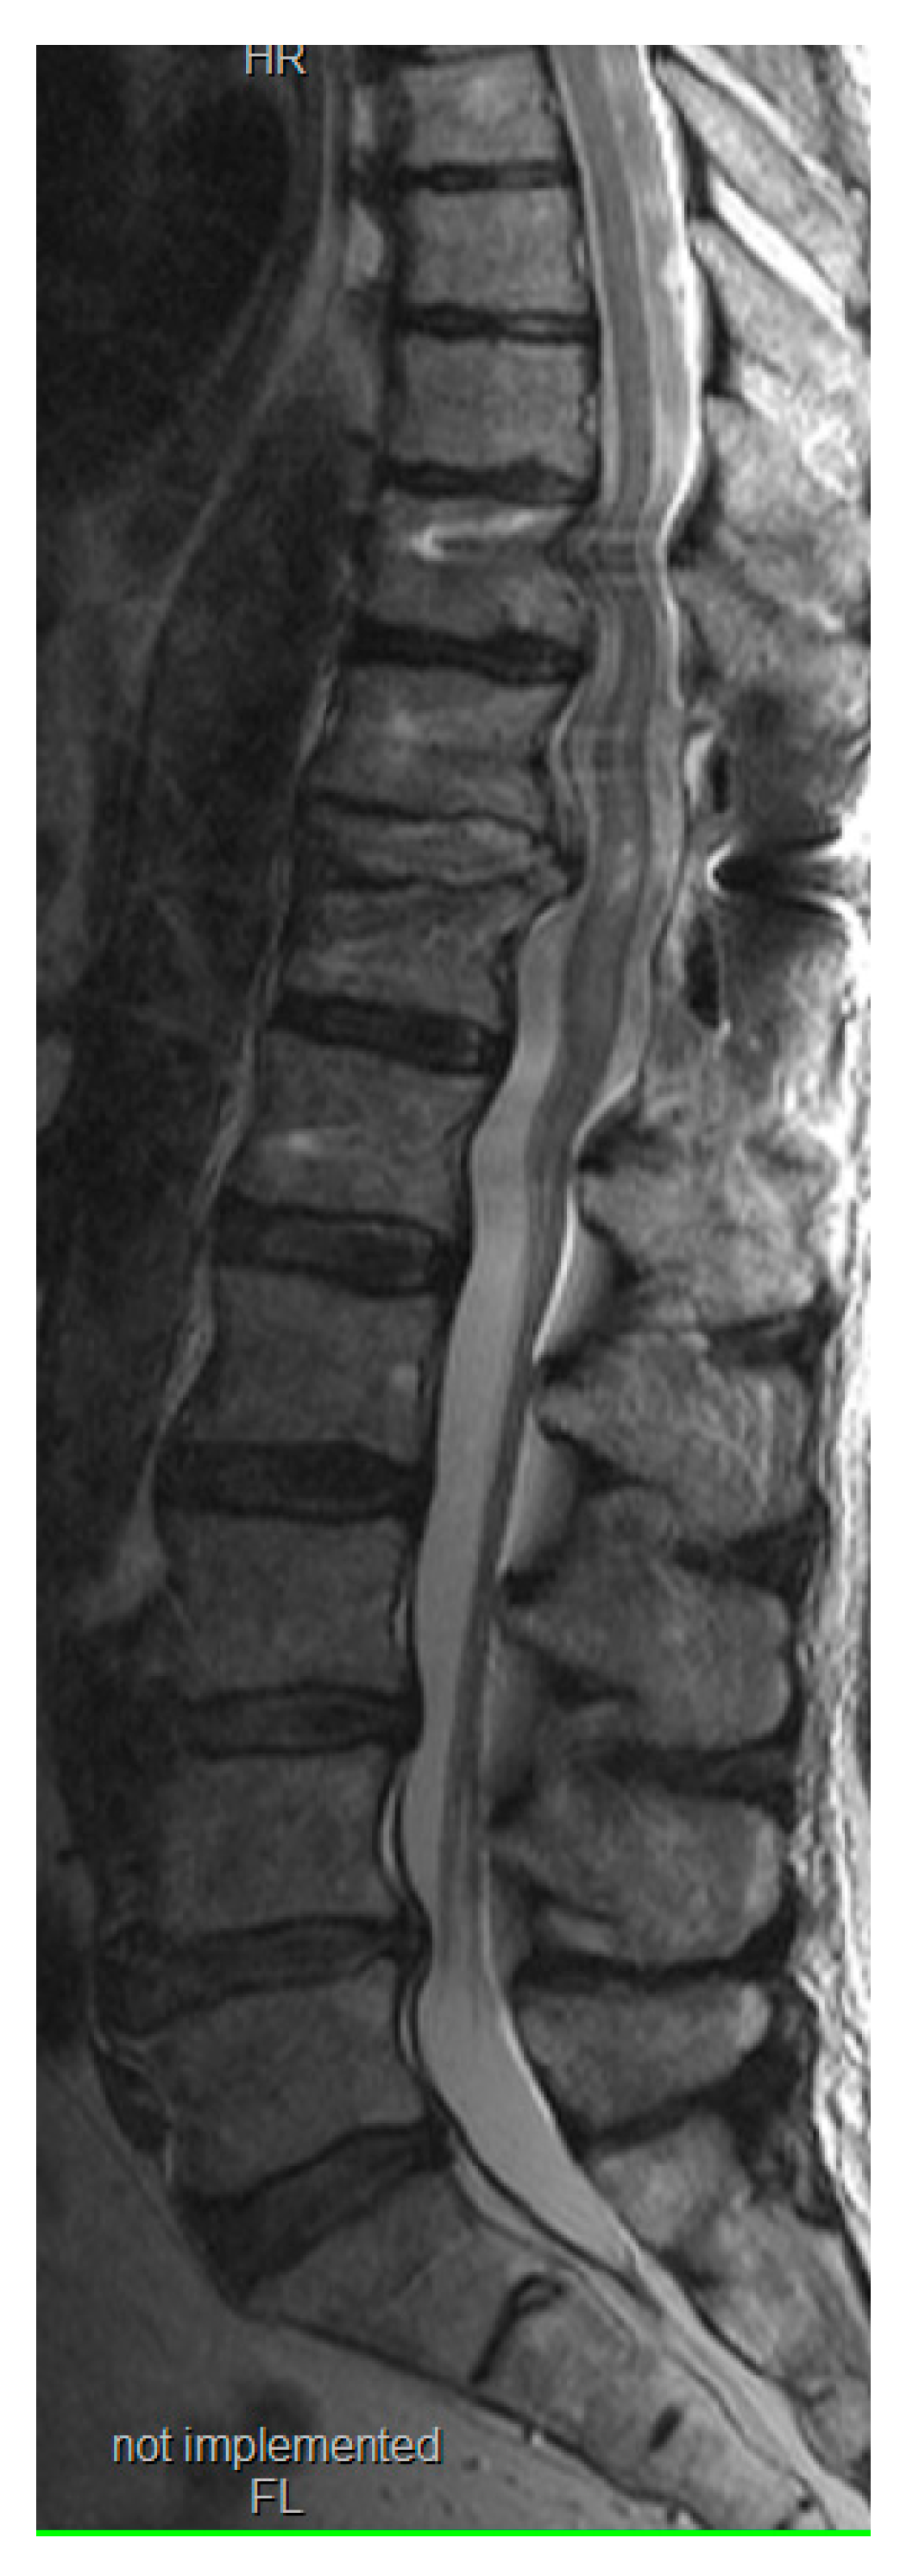

3. Results

This modified novel reduction technique was performed in 4 cases presenting with thoracic fracture-dislocations with complete paraplegia. The mean age of the patients presented was 32.2 (±7.1) years. All the patients presented in complete paraplegia. All the patients were operated as early as possible with mean time to surgery of 1.5 (±0.5) days. Upon utilization of the above-mentioned technique, we did not experience any technical difficulties in carrying out the reduction, and the post-operative period was uneventful in all the cases without any intraoperative complications such as dural tears or screw failure (Figure 6,7) [7]. The reduction was smooth, and we managed to avoid a 'second hit' to the already damaged spinal cord. (Figure 8) Due to the extreme compression of the spinal cord that occurs with spinal dislocation, patients remained paralyzed on follow-up visits until one year, although they did not experience back pain.

Figure 8. Postoperative T2 weighted magnetic resonance image revealing adequate decompression. Despite the slight artifacts from the screws, the medullary contusion is visible.